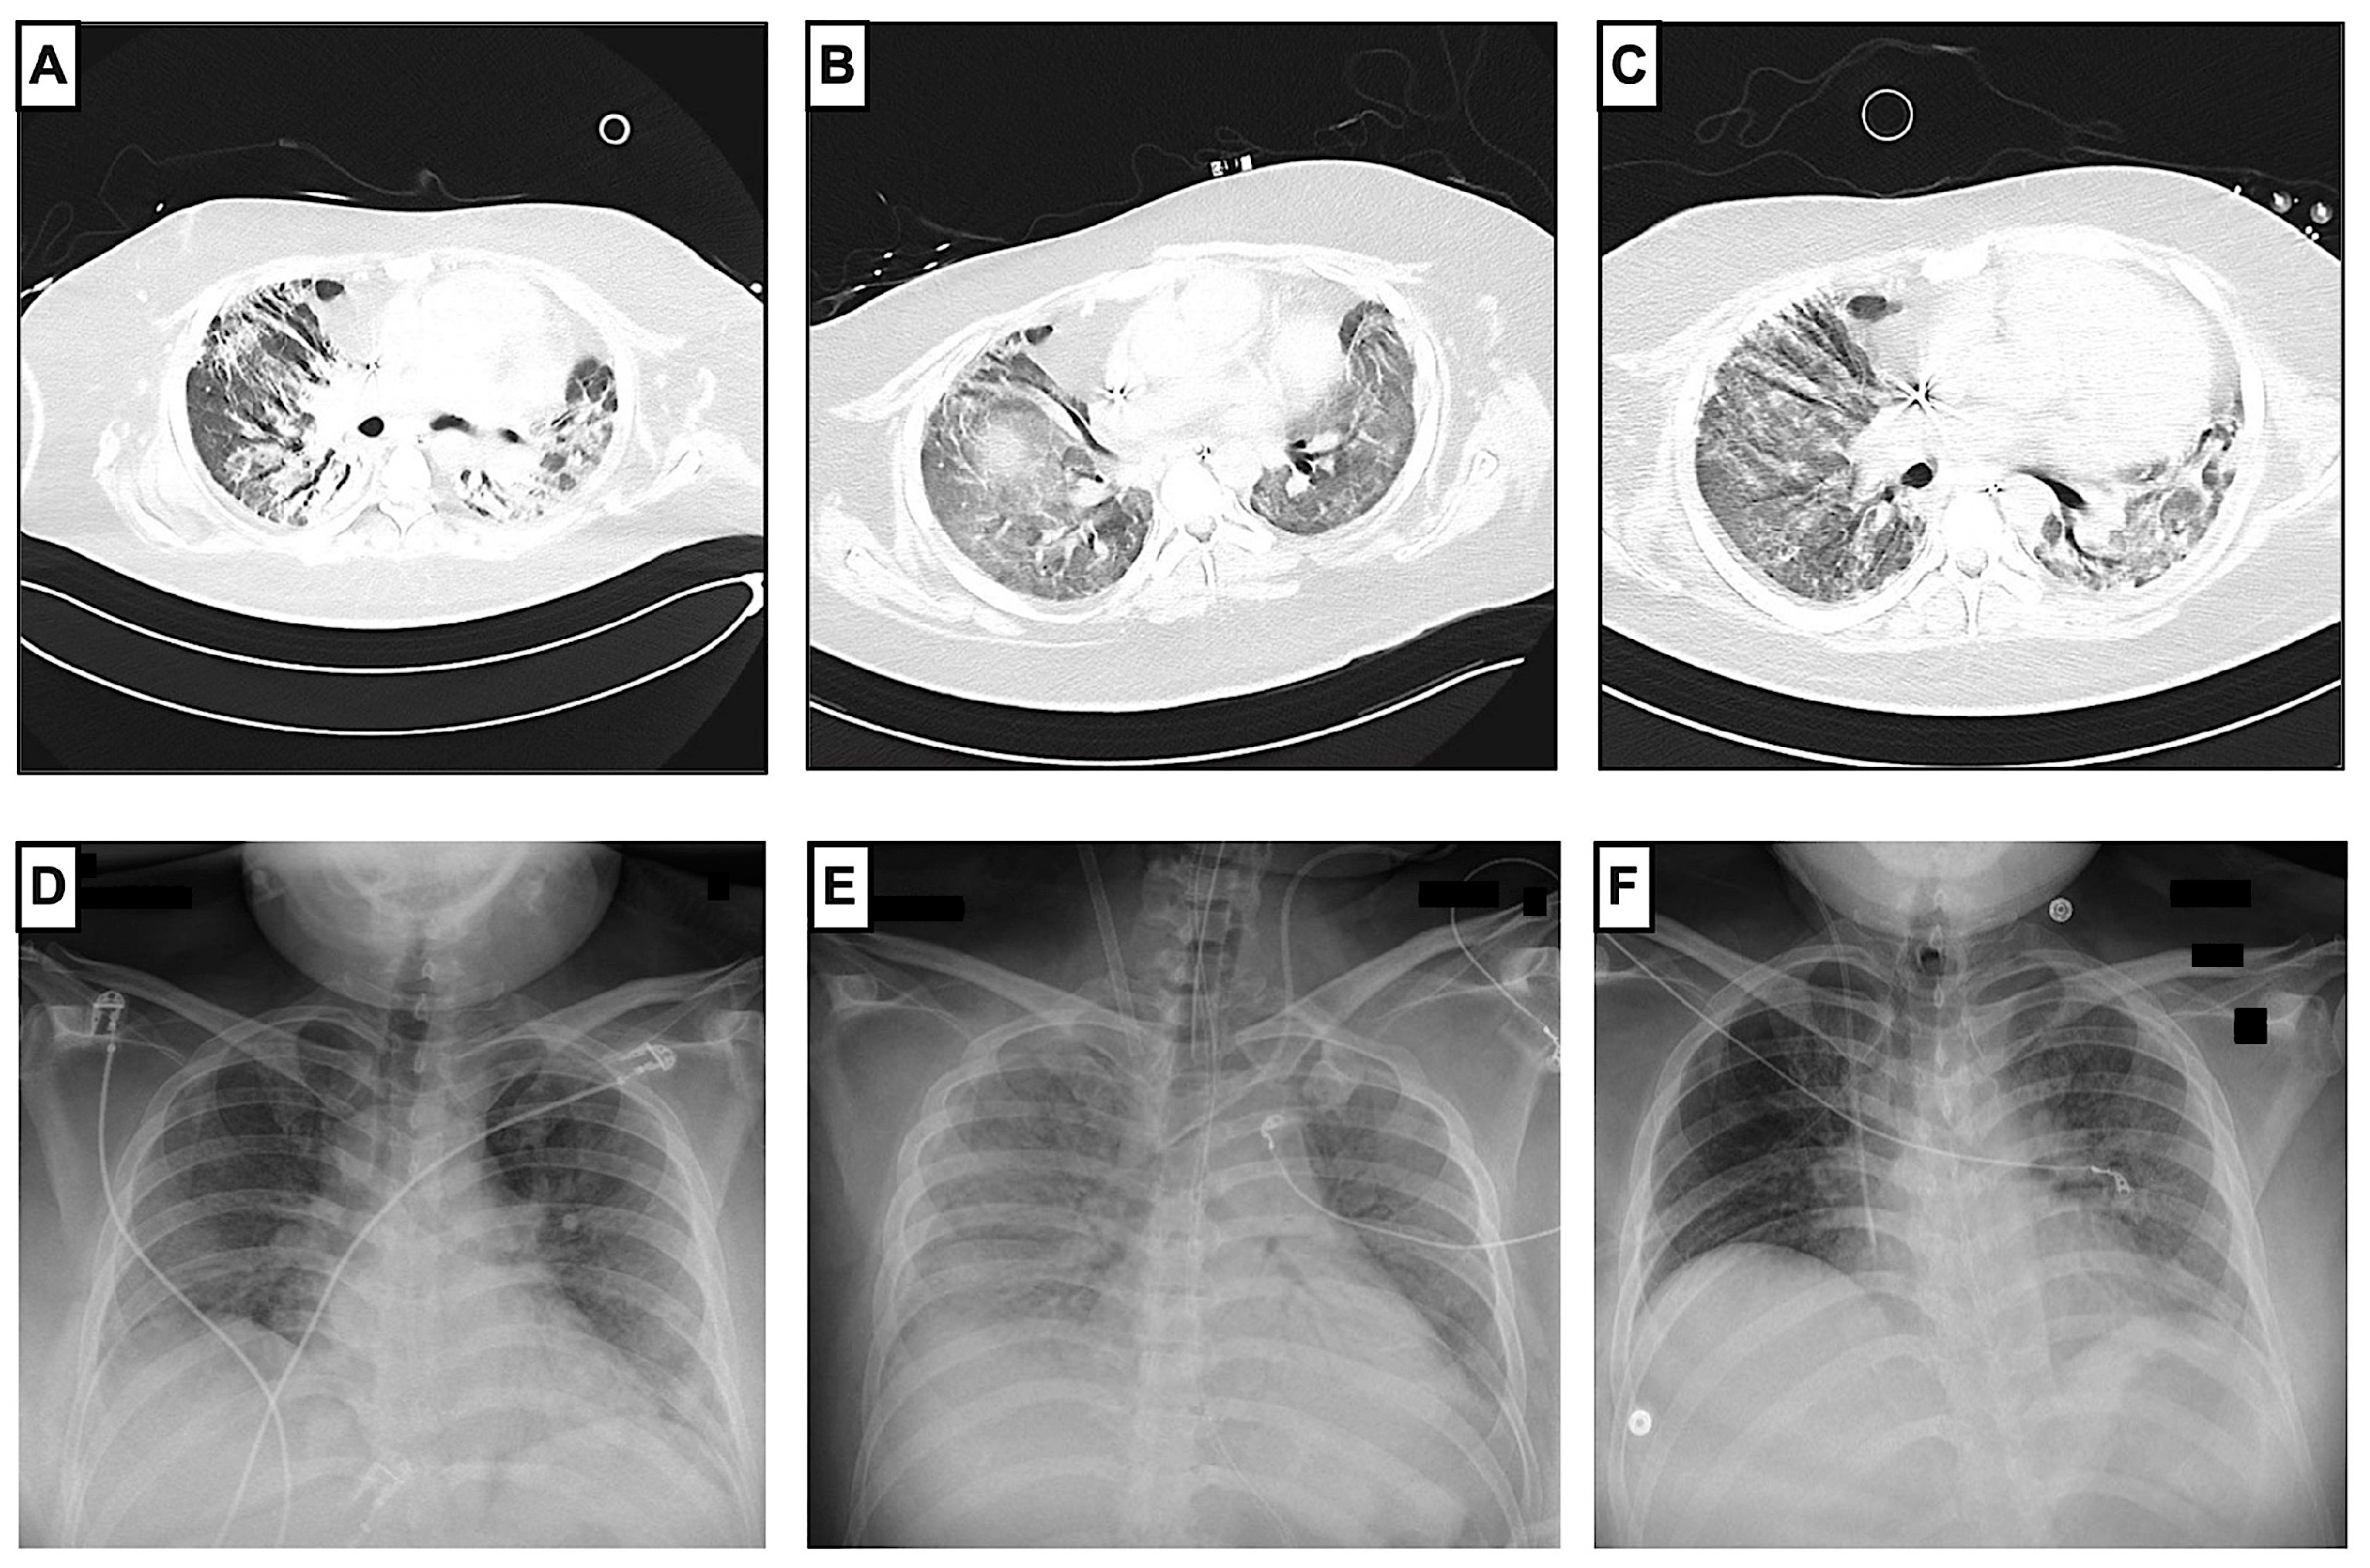

Figure 2.

Radiological progression of COVID-19 ARDS before and after administration of cyclophosphamide. Pulmonary CT scans (A–C) showed a regression of peribronchovascular consolidations and ground-glass opacity during the patient’s hospital stay. First pulmonary CT scan (A) was made on day 56, before the administration of cyclophosphamide, and showed findings compatible with organizing pneumonia in the context of COVID-19, with ground-glass opacities, peribronchovascular consolidations, and peripheral expansion of the bronchi. Second CT scan (B) was made on day 117 after vv-ECMO explantation and before the third administration of cyclophosphamide. A third CT scan (C) was made on day 128 in the non-ICU ward. Chest X-rays (D,E) show the progression during the ICU stay. The patient had chest X-rays at least once a day as a follow-up. Chest X-ray at ICU admission (D) on day 4 showed extended bipulmonary confluent consolidations. A chest X-ray after vv-ECMO implantation on day 14 (E) showed extended ground-glass opacity, and another chest X-ray at ICU discharge on day 125 (F) showed a regression of ground-glass opacity.

In addition, minute ventilation and tidal volume improved within days (Figure 3). On day 82, a second BAL with a differential cell count showed a reduction in lymphocytes and neutrophils, which could be interpreted as a treatment response (CC: 11.75 × 106; AM: 0.77; LYM: 0.06; NG: 0.15; eosinophilic granulocytes (EG): 0.02). Therefore, the cyclophosphamide and prednisolone regimen was repeated on day 84 (CP2). From CP2 to CP3, the respiratory situation of the patient continually improved. After reducing the sedative medication, the patient showed sufficient spontaneous breathing, which further improved ventilation mechanics. The vv-ECMO support was constantly declining and, consequently, vv-ECMO was successfully explanted with a total runtime of 85 days. After ECMO explantation, the patient had a P/F ratio of 238. Moreover, the entire ventilation effort (PEEP, driving pressure, ventilation mode, peak pressure) was continuously reduced and finally adjusted to a high-flow nasal cannula (HFNC). On day 117, a third BAL showed normal lymphocytes and slightly elevated neutrophils (CC: 2.35 × 106; AM: 0.82; LYM 0.10; NG 0.08), so the cyclophosphamide and prednisolone regimen was continued on day 119 (CP3). On the same day, the patient was decannulated and had adequate respiration. The patient’s general condition improved gradually, so he was transferred to the non-ICU ward on day 125 with 2 L per minute of oxygen supply. Normal lymphocytes and neutrophil granulocytes were detected in the fourth BAL (CC: 10.5 × 106; AM: 0.95; LYM: 0.03; NG 0.01; EG: 0.01). Pulmonary CT scans showed a regression of the peribronchovascular consolidations (Figure 2). Consequently, cyclophosphamide and prednisolone were repeated 62 days after the third administration (CP4).

After consultation with the pulmonology department, a bronchoalveolar lavage (BAL) was performed on day 49 (Table 1). The differential cell count showed extended lymphocytosis and neutrophilia (cell count (CC): 1.2 × 106; alveolar macrophages (AM): 0.08; lymphocytes (LYM): 0.42; neutrophil granulocytes (NG): 0.50). At that time, a pulmonary computed tomography (CT) scan showed extensive ground-glass opacities, peribronchovascular consolidations on both sides, and dilatation of the peripheral bronchi (Figure 2). Despite the evidence of dilated bronchi, there was no clear evidence of pulmonary fibrosis. The inflammation profile of the patient’s COVID-19 ARDS resembled non-specific interstitial pneumonia. Therefore, empiric therapy with a single dose of 2000 mg of intravenous cyclophosphamide and 1000 mg of prednisolone was established on day 56 (CP1). Under CP1, the patient’s respiratory condition improved remarkably. A few days after CP1, an increase in tidal volume and P/F ratio (>140) was observed. These improvements in the respiratory situation made it possible to reduce ECMO support (sweep gas flow of 2–4 L/min and blood flow of 2 L/min). At the same time, a slow but significant increase in tidal volume from 196 to 712 mL without an increase in pressure support was observed.